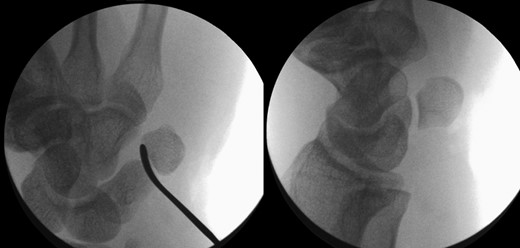

The patient was taken to theatre the following day where a closed reduction of the dislocated pisiform was attempted, however it was unsuccessful. Therefore we then proceed to an open reduction. This was performed through a volar approach through the flexor carpi ulnaris tendon where the piso-hamate joint was exposed and a capsular release performed. This allowed the pisiform to reduce back in to the anatomical position Fig 3. The wrist was immobilized in a neutral position. The patient was followed up in the clinic in two weeks, six weeks, three and six months. The check X-ray performed at the end of six months demonstrated the pisiform remain well reduced, Fig 4. He subsequently regained full a range of motion within the wrist and was further discharged from the clinic.

Image intensifier pictures showing reduction of dislocated pisiform bone.

Radiograph at 3 months showing pisiform bone anatomically reduced and maintained.